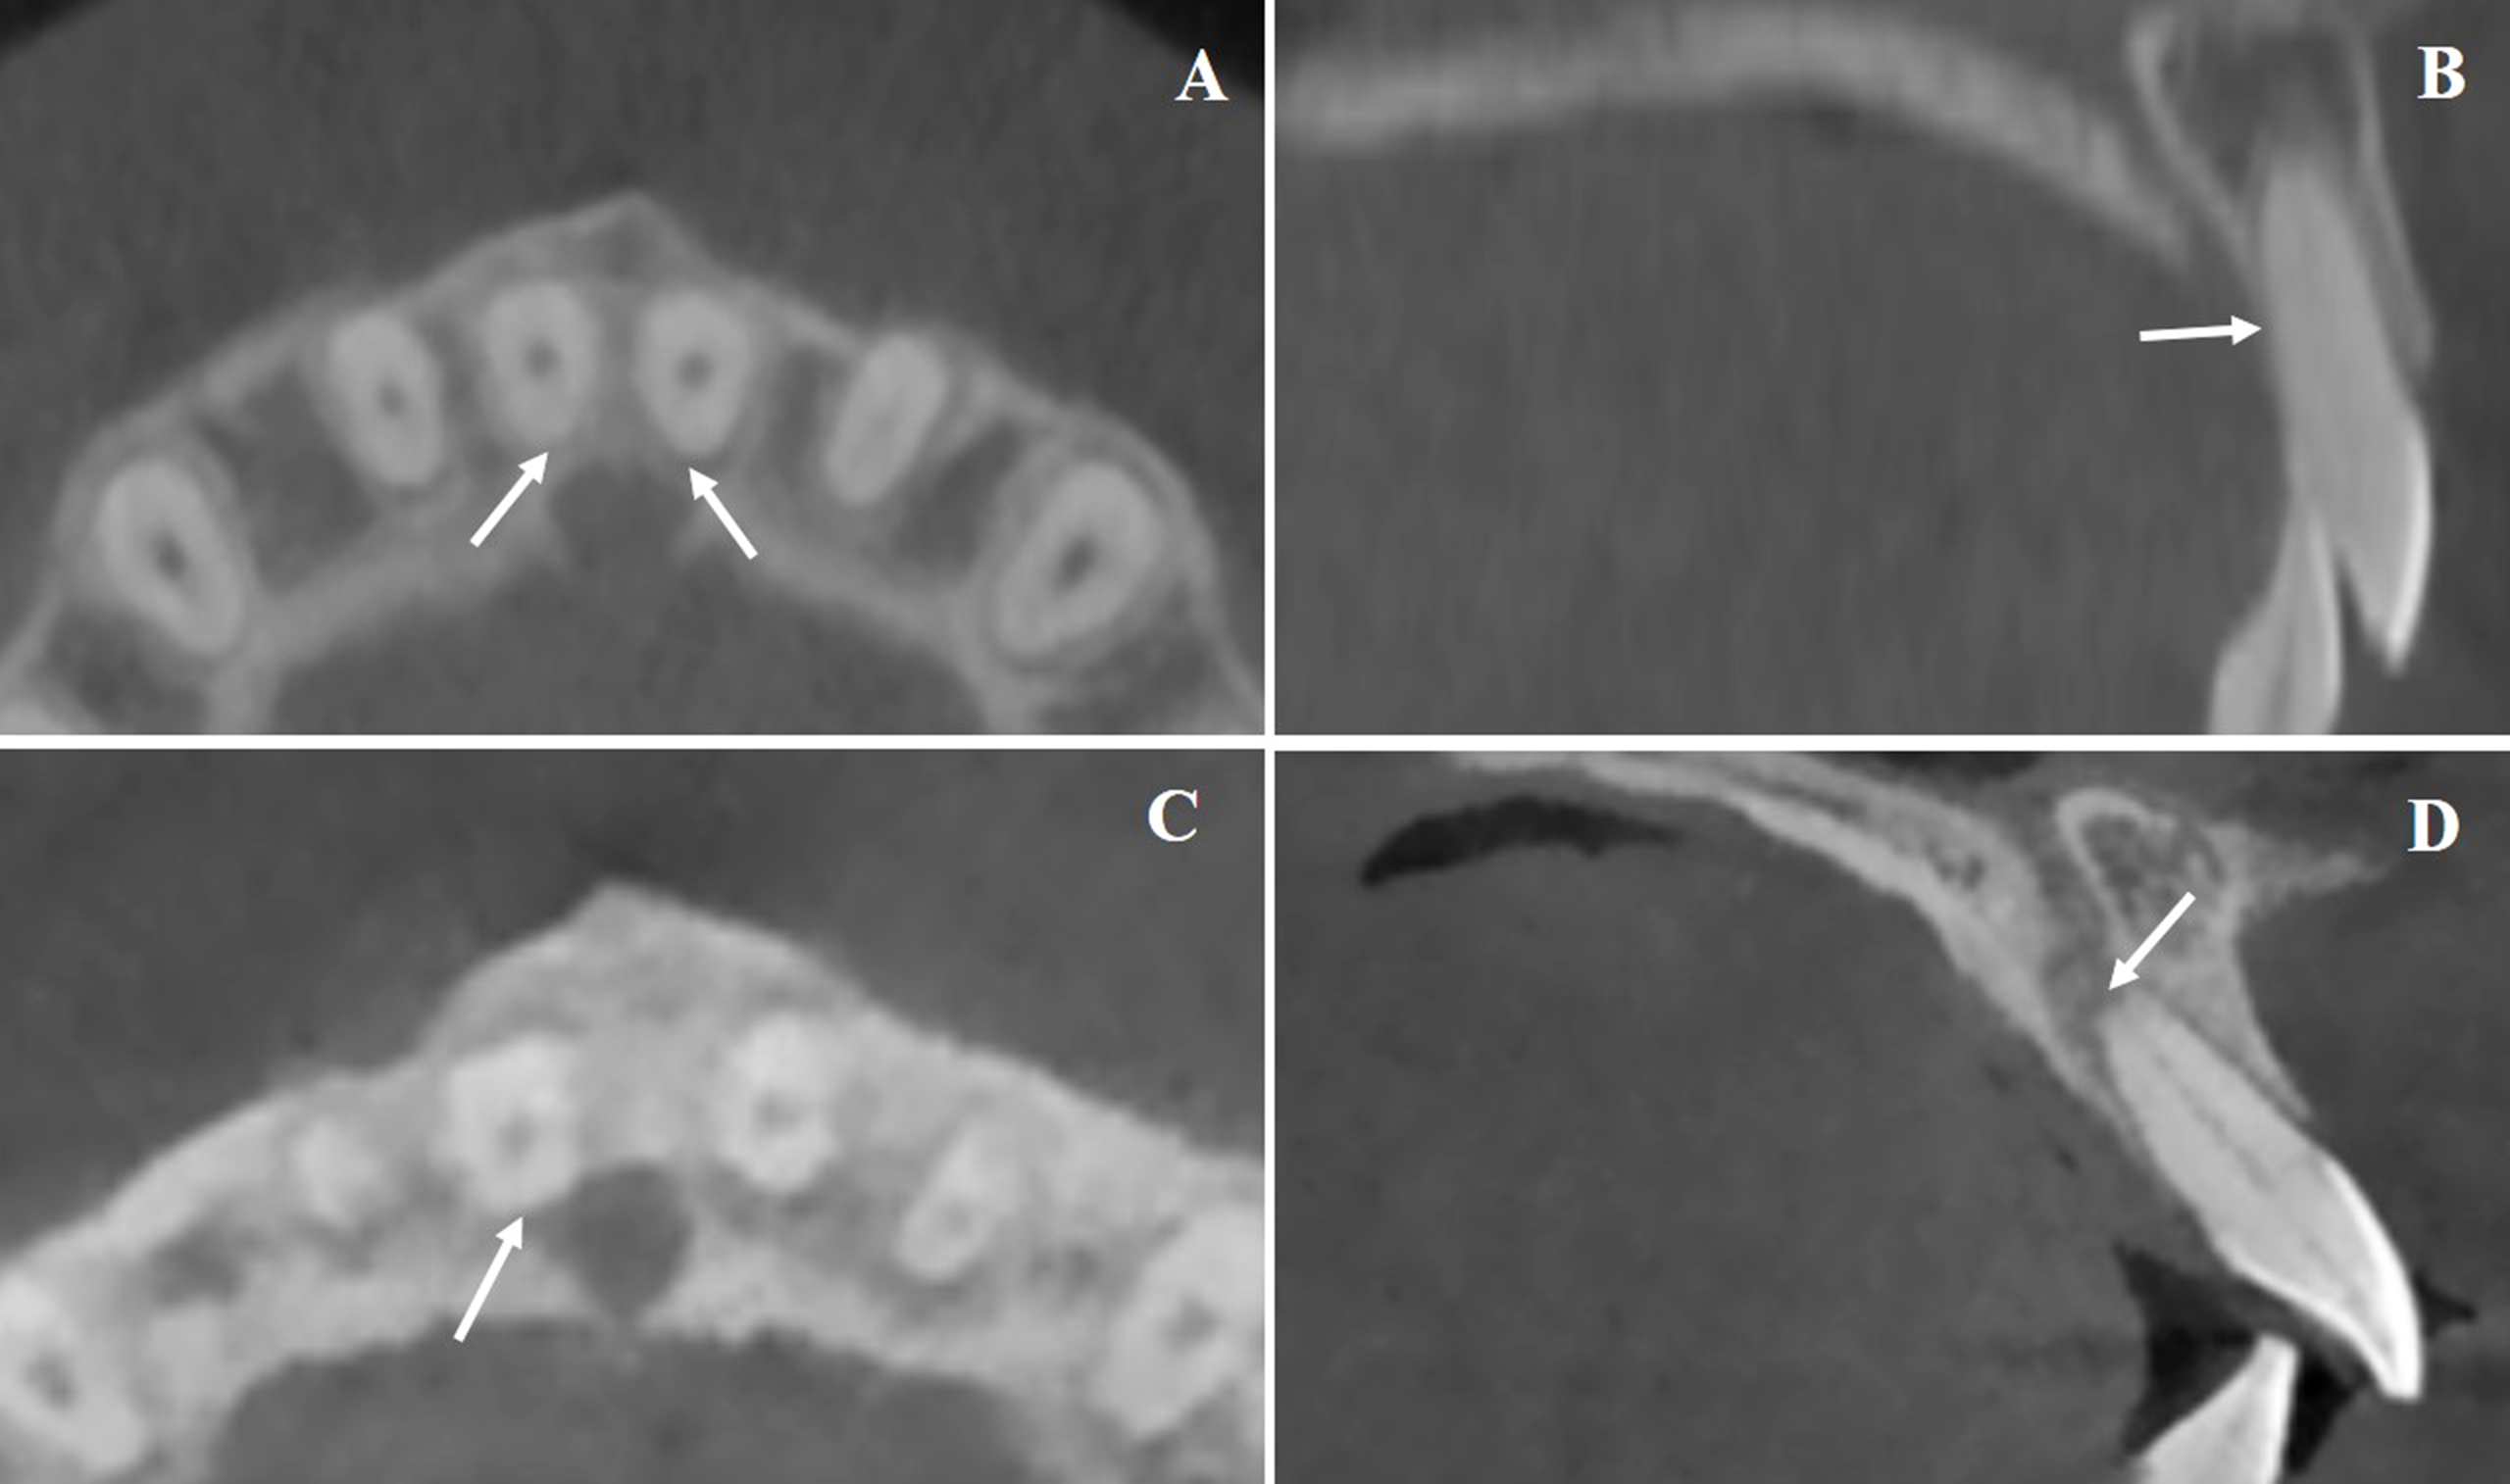

Based on CBCT evaluation, post-treatment root-to-IC relationships were categorized as follows: separation, increased distance between root and IC cortical boundary; approximation, root nearing the IC without contact; contact, root abutting the IC cortical margin (distance = 0, Fig. 2A-B); and invasion, root partially or fully penetrating the IC cortical plate or lumen (distance < 0), with remaining CBW noted as zero if the lumen was involved (Fig. 2C-D).

Representative Patterns of U1 Root and Incisive Canal Proximity. A and B. Representative CBCT images showing direct contact between the incisor root and the lateral wall of the incisive canal (highlighted by arrows). C and D. Examples illustrating root invasion into the IC lumen, with cortical disruption clearly visible (indicated by arrows).